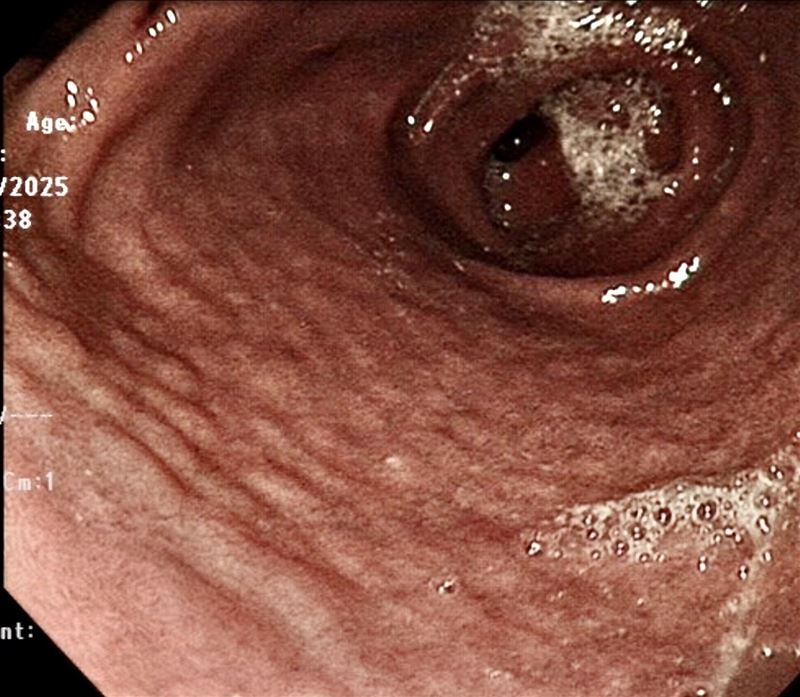

一名15歲的男孩,突然嚴重吐血住院,誰也沒料到胃鏡鏡頭推進去,看到的竟是一幅令人觸目驚心的畫面:整片胃黏膜布滿圓圓隆起的小丘,像一床鵝卵石鋪在胃壁上,還有一個正在出血的潰瘍。最終切片報告揭示,這是幽門螺旋桿菌感染,而且病程已進展到癌前病變階段。

胃黏膜「鵝卵石樣」是感染訊號 切片驗出癌前病變

兒童腸胃科醫師洪華希近日在臉書粉專分享這起臨床個案,指出幽門螺旋桿菌早在1994年就被世界衛生組織(WHO)列為第一級致癌物,多項大型研究顯示全球約80%的胃癌與它有關。這名男孩胃黏膜出現的結節樣鵝卵石改變,是感染後胃部長期發炎的典型表現,切片報告更顯示已出現「低度異形增生」,這是胃癌發展路徑上的一個警示站。